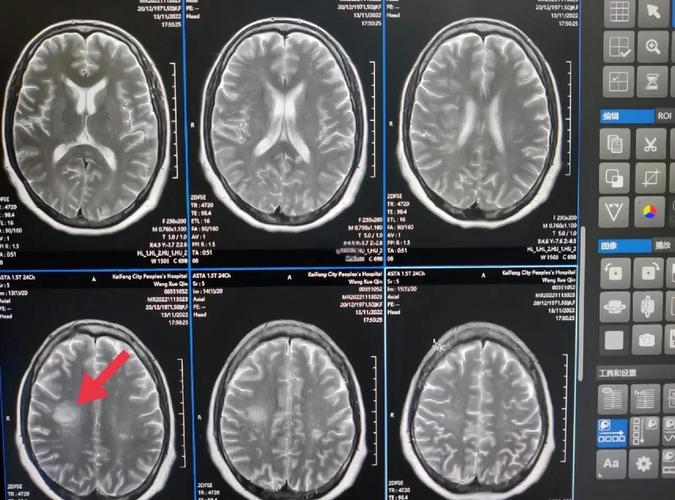

(图片来源网络,侵删)

- 影像学检查是金标准:

- 头部CT平扫:在发病早期(6小时内)可能看不到明显异常,但可以排除脑出血,发病24小时后,梗死区域会表现为低密度影。

- 头部MRI(磁共振):是诊断脑梗最敏感、最准确的方法,特别是DWI序列(弥散加权成像),能在发病后几分钟到一小时内就显示出高信号,非常敏感。FLAIR序列和T2序列也能清晰显示梗死灶的范围和位置。